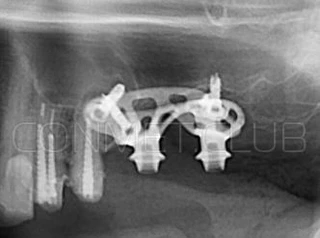

Первый вывод к которому мы пришли, это то, что для данных конструкций имплантатов сохранять внутренний интерфейс с шестигранником и конусом Морзе нецелесообразно из-за ограничения возможностей современной 3D печати титана. Кроме того, техническая обработка после 3D печати такого интерфейса представляет значительные трудности и ведет к неоправданному увеличению цены. Поэтому пришли к единодушному мнению, что лучший вариант-это опорные элементы полностью повторяющие абатменты-мультиюниты.

Второй, и наверное главный вывод-решение - моделированием и конструированием индивидуальных, субпериостальных имплантатов должен заниматься инженер-конструктор с большим опытом в медицине и знаниями индивидуальной анатомии челюстно-лицевой области на уровне хорошего хирурга. При этом все-равно должно осуществляться тесное и постоянное взаимодействие с хирургом, который будет проводить операцию.

Посмотрите на небольшом клиническом примере новый подход к конструированию имплантата по сравнению с имплантатами описанными в начале этой статьи.